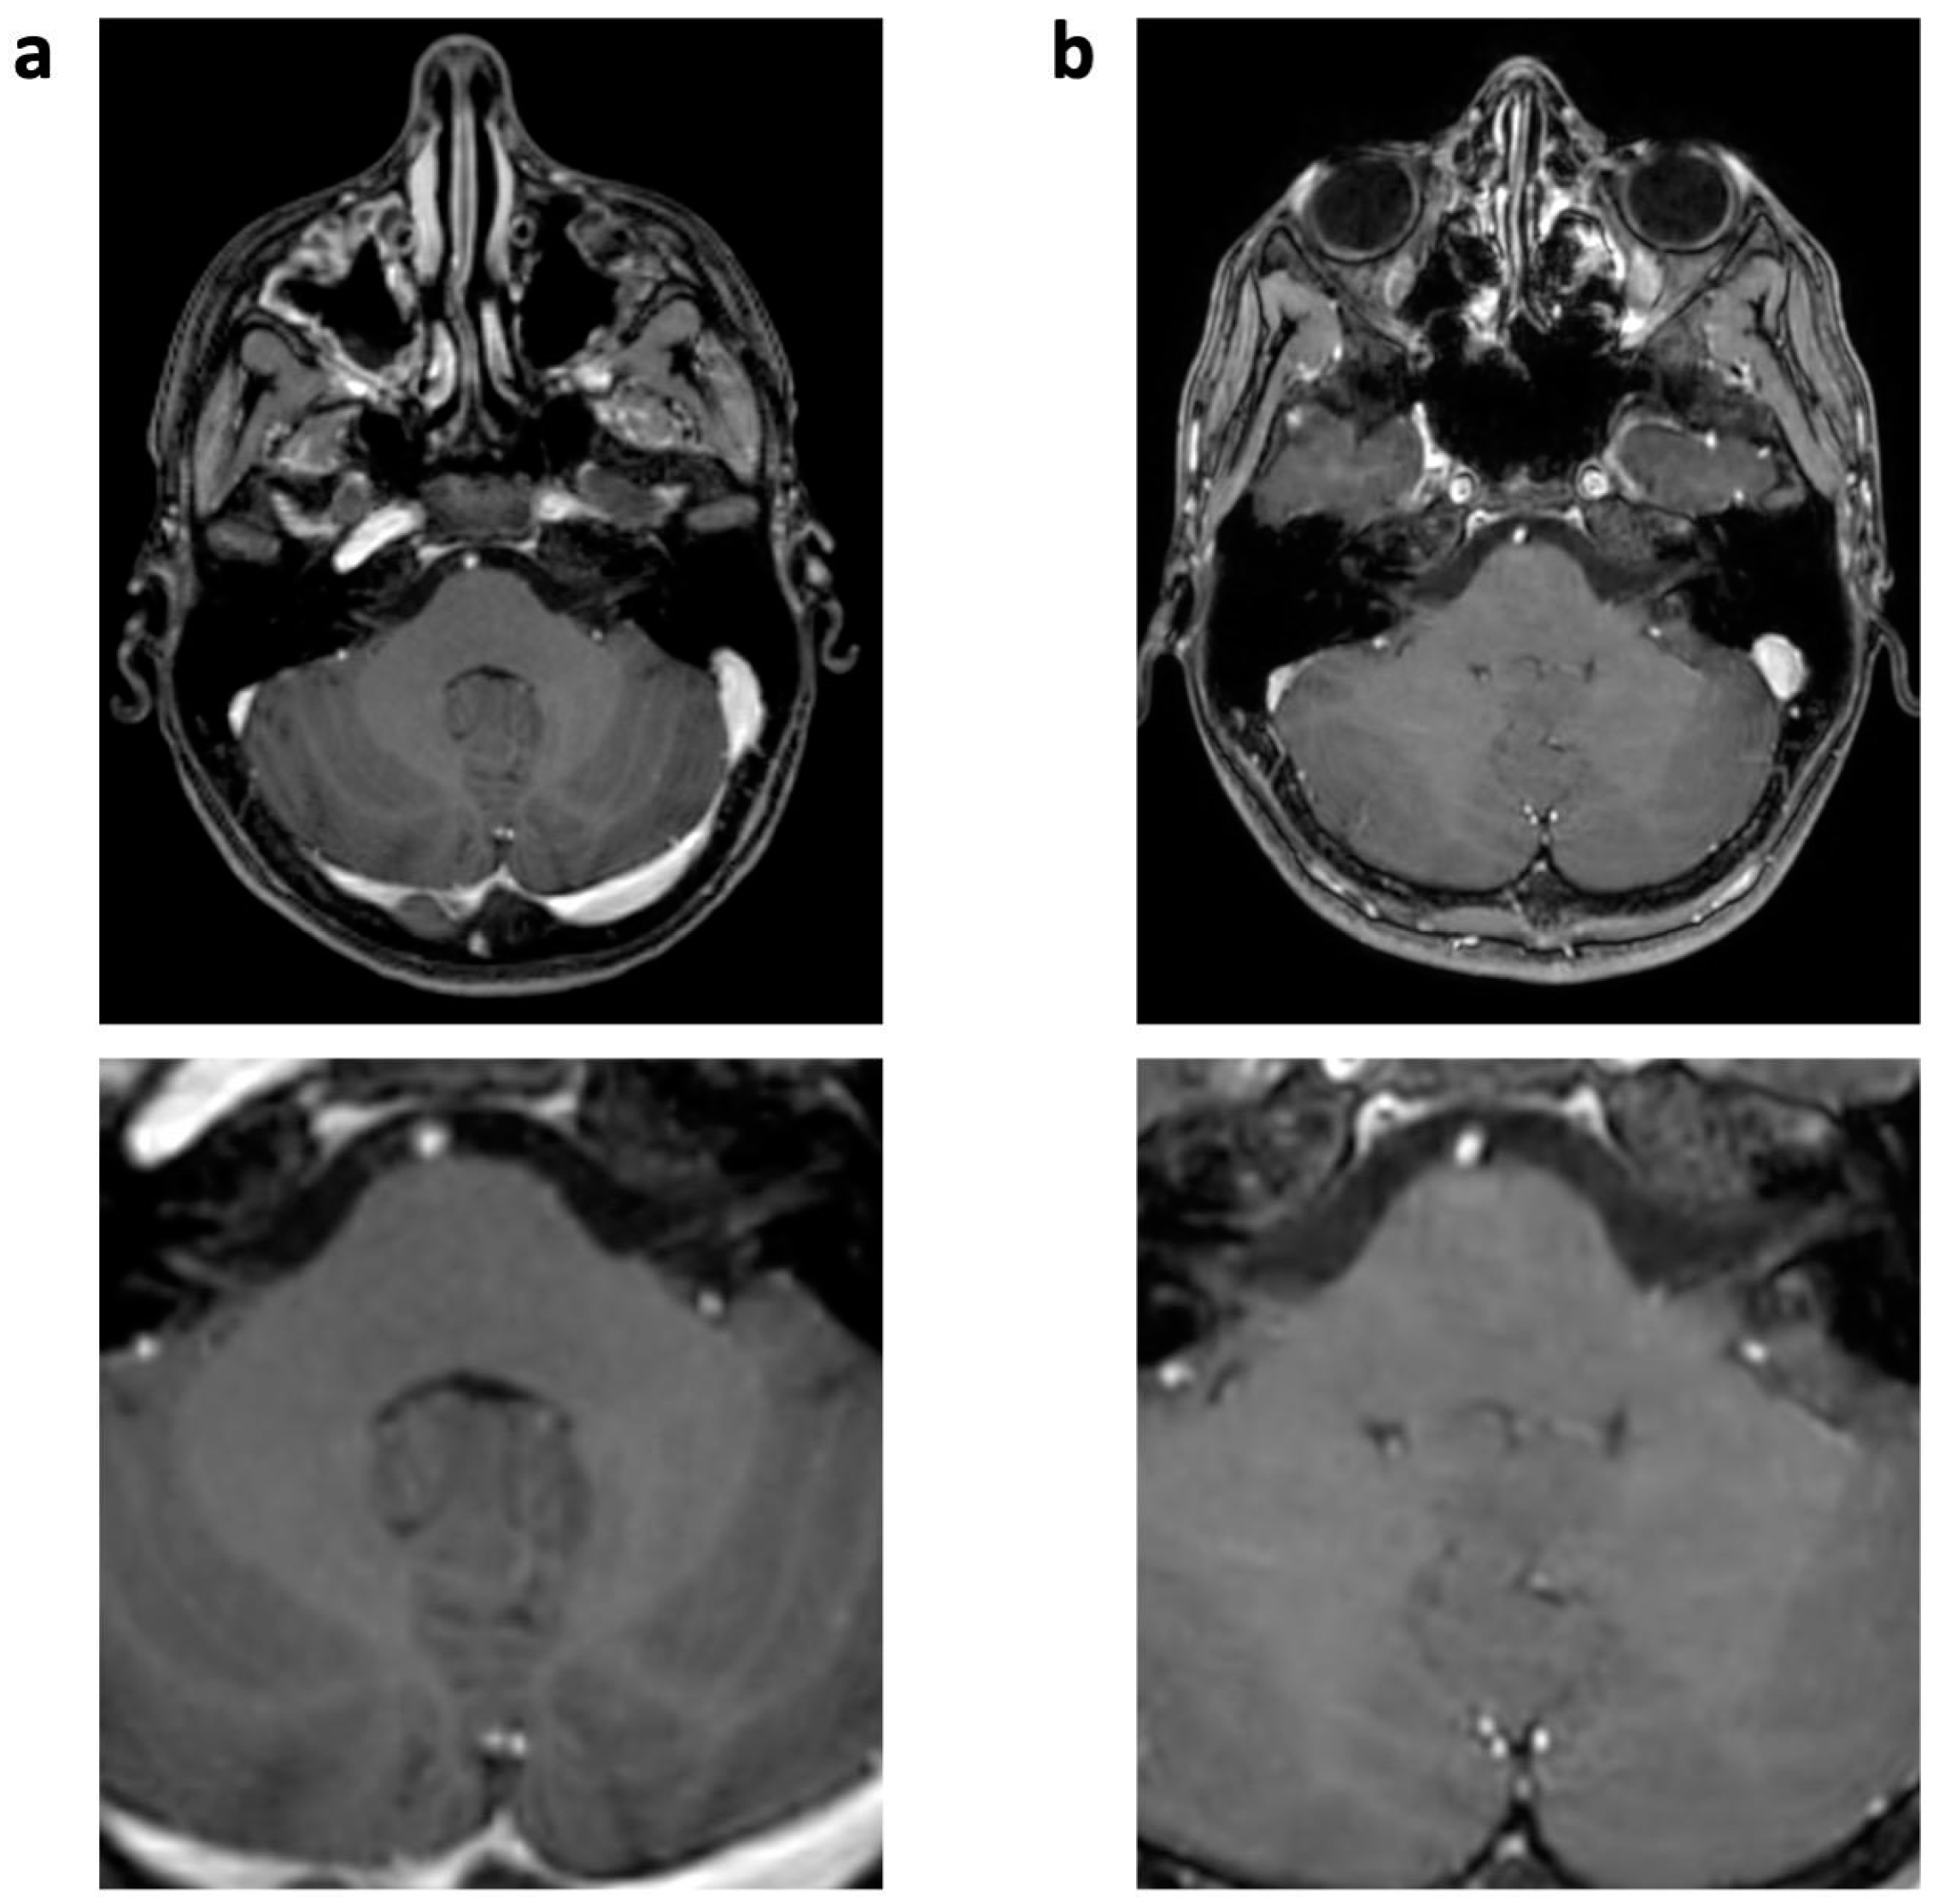

Figure 2.

Enhanced 3D T1 TFE images of an 18-year-old male patient with ganglioglioma (not shown). Reconstruction artifact with thin oblique geometrical streaks is seen in SENSE 3D T1 TFE ((a), post-surgery); not present in CS 3D T1 TFE (b). White box indicates magnification.